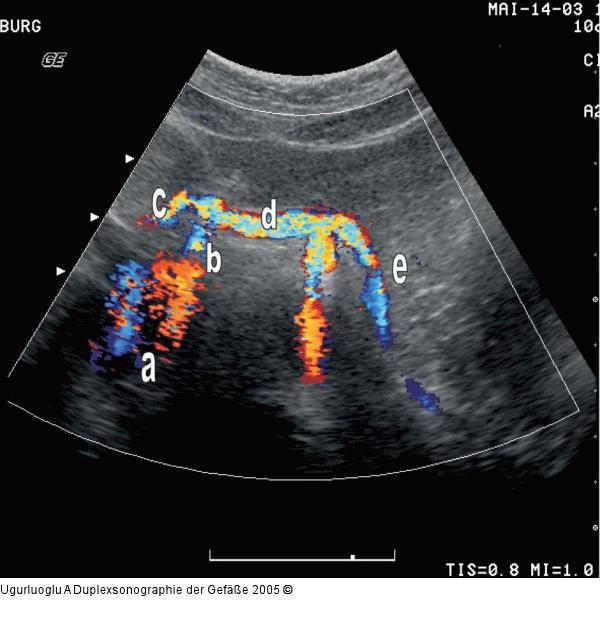

Abbildung 4: Duplexsonographie - T. coeliacus a) Aorta abdominalis, b) Truncus coeliacus, c) Arteria hepatica communis, d) Arteria lienalis, e) Arteria gastrica sinistra. Transversale Schnittführung |

a) Aorta abdominalis, b) Truncus coeliacus, c) Arteria hepatica communis, d) Arteria lienalis, e) Arteria gastrica sinistra. Transversale Schnittführung |